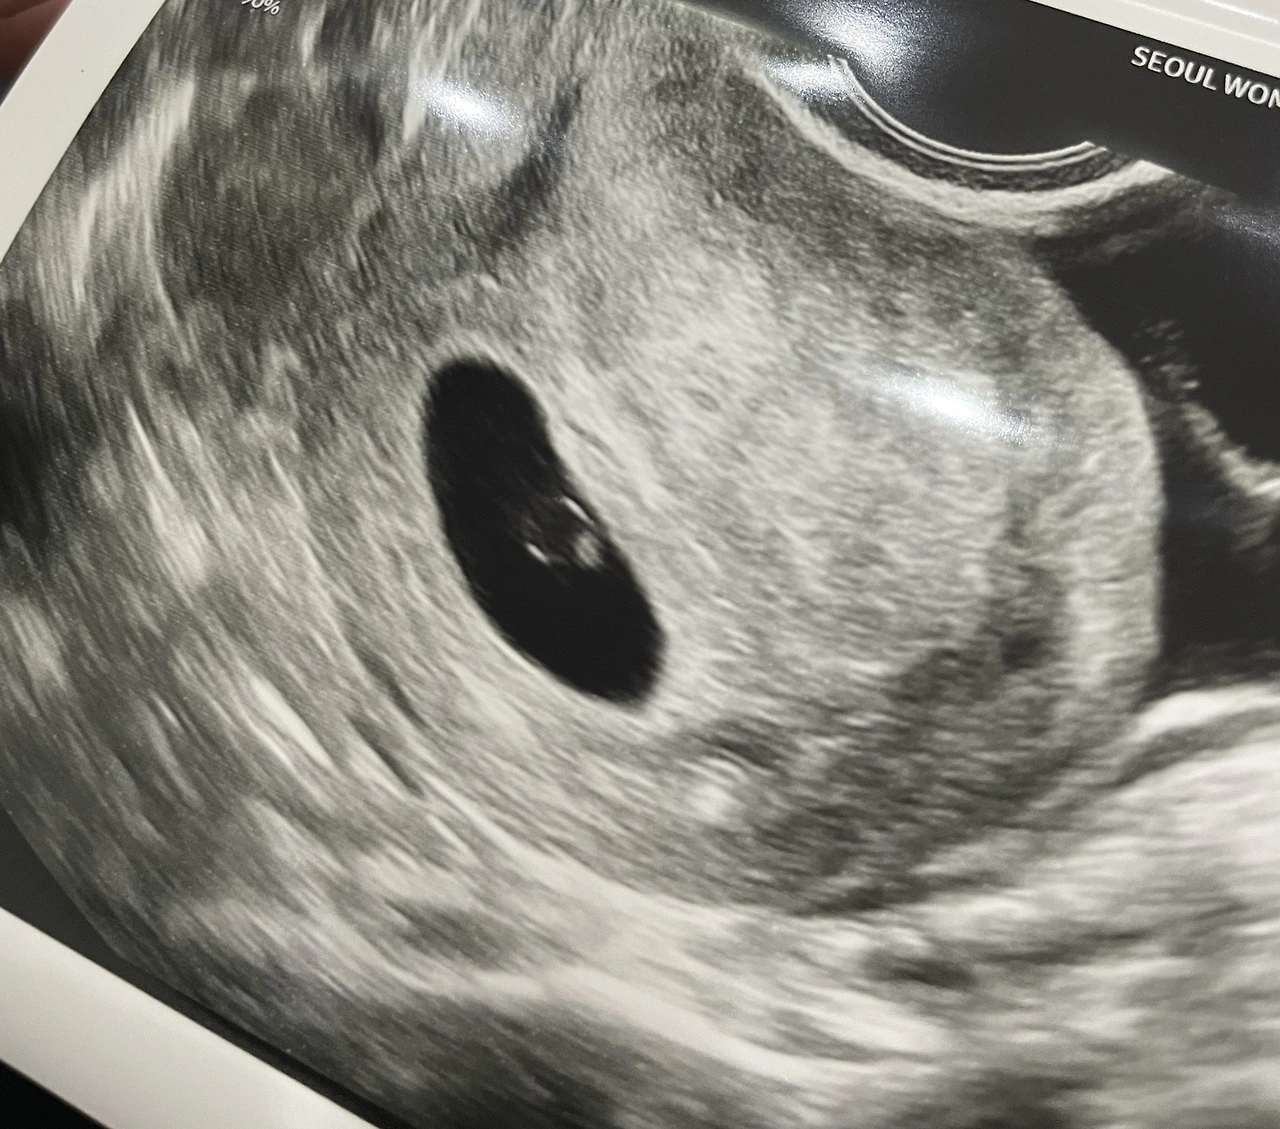

잔뜩 긴장하고 누웠는데, 초음파 화면 속 아기집과

난황이보였다!

첫 초음파 5주 5일

의사는 아기도 보인다고 했다.

아기의 크기를 측정해 줬는데 고작 0.22cm였다.